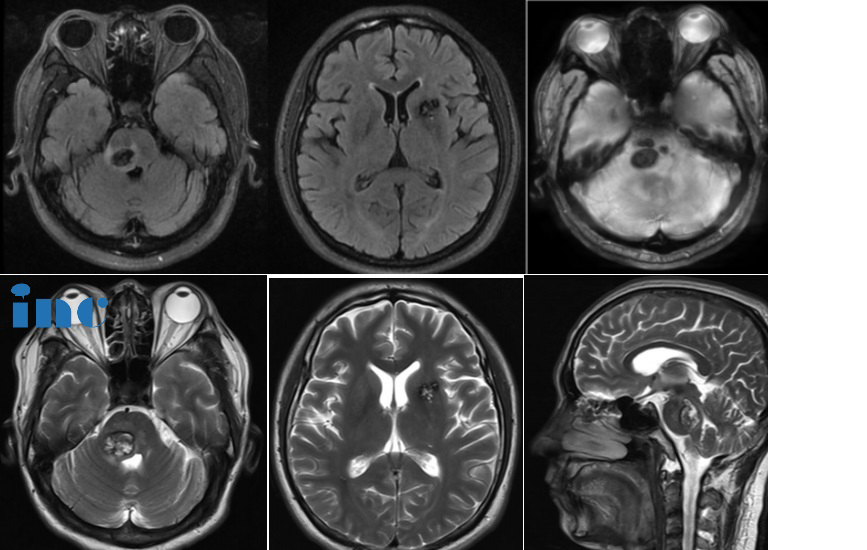

43岁男性——多发海绵状血管瘤合并脑干出血

“对于这种内源性出血的海绵状血管畸形,手术切除率将一如既往地达到全切(或99.9%)”

43岁的潘先生2023年7月中旬因为持续多天的头晕、左侧肢体麻木就医入院检查,简单查体后却未发现异常。在医生的建议下进行进一步的辅助检查,却没想到竟然是脑子里面出了“问题”,头颅CT提示脑干出血,MR显示潘先生颅内有两处脑海绵状血管瘤,一个位于脑干-脑桥位置,一个位于基底节位置,手术风险都很大,考虑到目前症状并不严重,医生建议暂行保守治疗。保守治疗三个月期间,潘先生左侧肢体麻木僵硬依旧存在并且出现了轻微的面瘫。潘先生开始多方查询能够顺利为自己手术的主刀医生。

视频咨询巴特朗菲教授:

在查看了潘先生的MR影像核磁胶片后巴教授回答了关于手术时机的问题,目前潘先生的脑干位置的海绵状血管瘤出血已经吸收,并且形成了局部瘢痕,病灶位于脑干偏中间的位置。此时手术的话,手术对于面神经和外展神经的风险会更大。潘先生可以先观察3个月左右,结合后续的影像核磁和症状情况,后续选择合适的手术时机。如果后续出现手术指征的话,巴教授可以为他成功手术,不用过于担心。

而关于脑海绵状血管瘤保守期间,自己的正常生活是否有需要特别注意的,比如负重能力需要控制在多大的范围内。